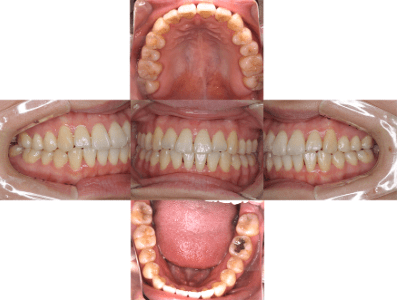

治療前

• 初診時年齢:25歳

• 主訴:開咬

• 診断:舌癖を伴う歯性の開咬

• 抜歯箇所:非抜歯

• 治療内容:下で前歯を押してしまい、前歯で咬めない状態でした。マウスピース型カスタムメイド矯正歯科装置(製品名インビザライン 完成物薬機法対象外)で、奥歯を低くしつつ、前歯を伸ばし、前歯で咬めるようになりました。

• 治療期間:2年6ヶ月

• リスク:ブラックトライアングル(歯と歯の間と歯ぐきの間の三角形の隙間)が強くでる場合がある

• 費用:99万円